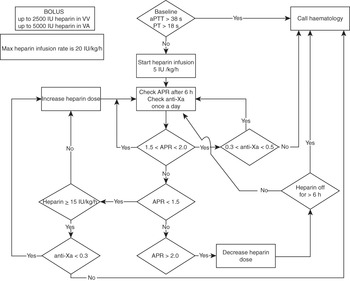

Standard decision trees should be developed to support staff at the bedside. This should include when to call the haematology department (see example in Figure 7.3).

Figure 7.3 Example of a decision tree to support staff at the bedside. VA, veno-arterial; VV, veno-venous; PT, prothrombin time.